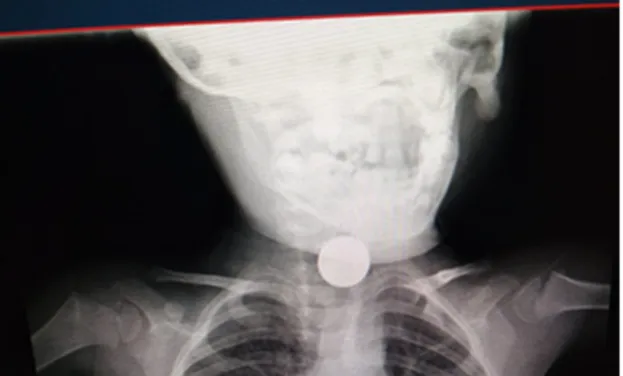

Arrivato al presidio del Vomero vengono effettuati nuovi controlli e, da un attento esame radiografico, si capisce che il corpo estraneo fermatosi in esofago è una disk battery che, ormai, è tenacemente aderente all’esofago con una progressiva necrosi dei tessuti.

Non c’è tempo da perdere. Il piccolo viene portato in sala operatoria, ma i numerosi tentativi di rimozione per via endoscopica risultano vani. Si decide, quindi, di optare per un approccio chirurgico direttamente attraverso il collo nell’esofago cervicale. Un intervento più invasivo che però ha consentito la rimozione dell’oggetto senza che provocasse ulteriori danni.

La batteria, infatti, era ormai incastrata nell’esofago e rischiava di perforare la trachea e danneggiare l’aorta. Il piccolo è ora ricoverato in terapia intensiva non più in pericolo di vita, ma ancora in prognosi riservata e sotto stretto monitoraggio per valutare l’evoluzione dei danni riportati all’apparato digerente.